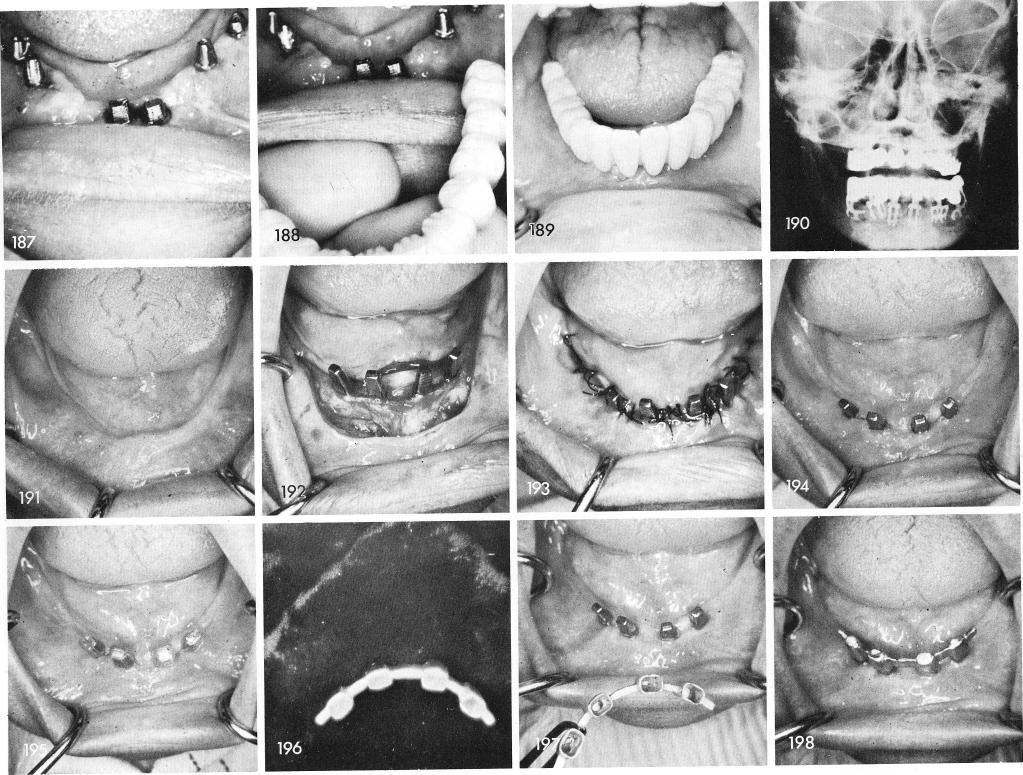

This case has already been in the mouth of my secretary for over seven years, figs. 187, 188, 189. A postero-antero roentgenogram reveals quite clearly the curvature of the blades around the arch and the restoration they have been supporting, fig. 190.

It is possible, at times, to utilize only the anterior portion of the totally edentulous mandible, fig. 191, for denture support using two double posted blades, figs. 192, 193, 194. Plastic copings are fitted over the blade posts, fig. 195, to facilitate an Andrews type bar system joined by four copings, fig. 196, which is cemented over the protruding implant posts, figs. 197, 198,

1 Postero-antero roentgenogram revealing curvature of mandibular blades